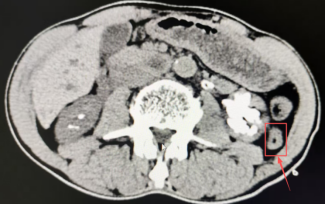

图:患者术前影像学检查

二期手术由罗力教授与蒋勇军主任分别带队,采用斜仰卧位(“骑马射箭”体位),同步进行经皮肾镜与输尿管软镜联合碎石。双镜配合下,中下盏结石被基本清除。